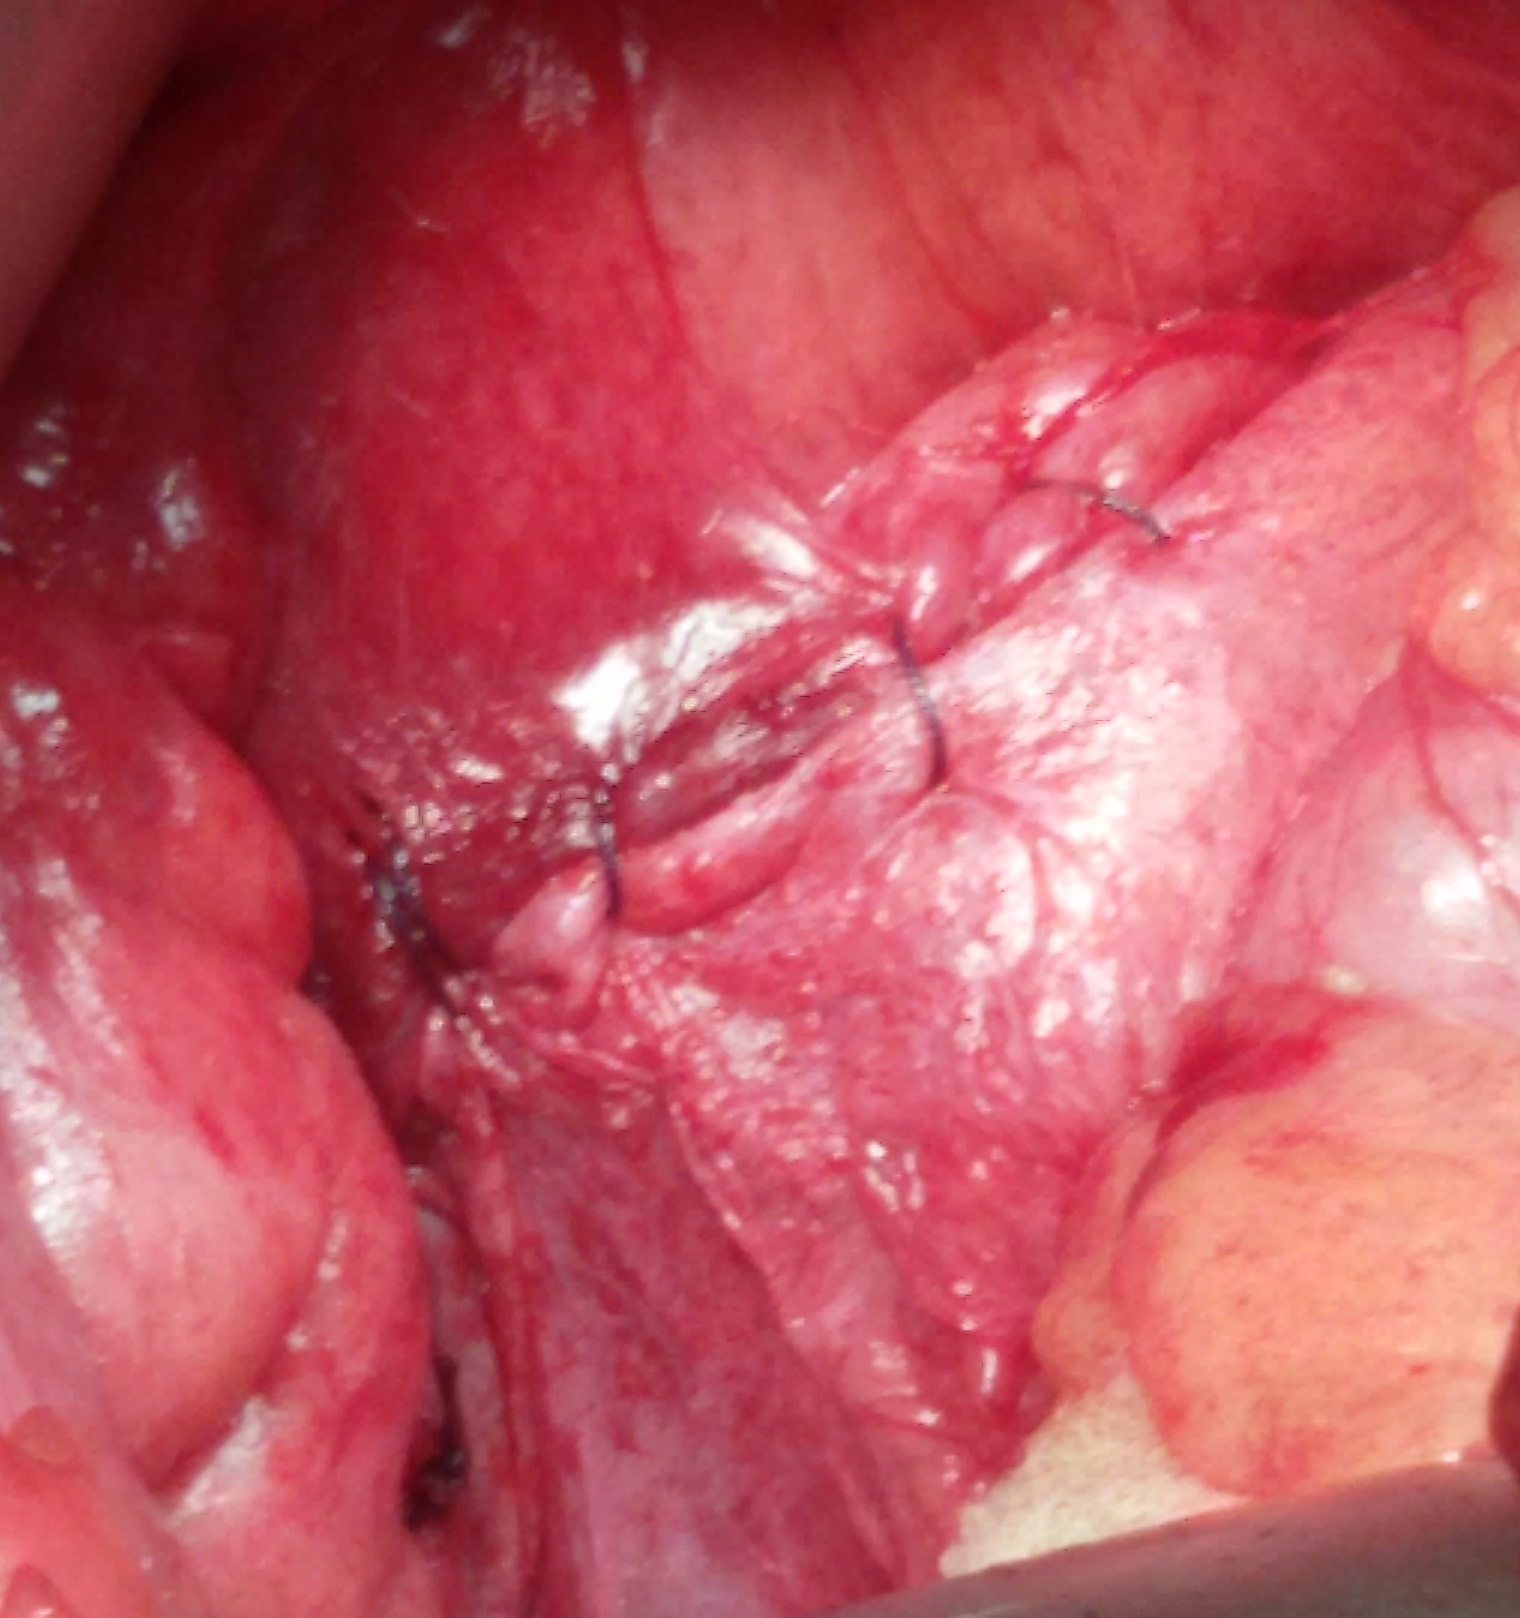

18.4.14 A VVF (poor 45 years old lady) following an abdominal hysterectomy in UP, was repaired abdominally. The fistula was high in the fundus of the bladder.